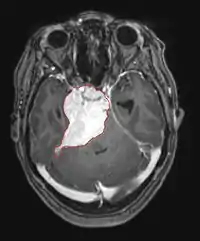

Hjernemetastaser

Hjernemetastaser er de mest almindelige intrakranielle neoplasmer hos voksne og er ti gange hyppigere end primære hjernetumorer. De træder til 20 indtil 40 procent af voksne med kræft og er hovedsageligt forbundet med lunge- og brystkræft og melanom . Disse læsioner skyldes spredning af kræftceller gennem blodbanen og forekommer oftest ved krydset mellem gråt og hvidt stof, hvor tværsnittet af blodkar ændres, hvilket fanger tumorcelleemboli . 80 procent af læsionerne forekommer i cerebrale hemisfærer, 15 procent i lillehjernen og 5 procent i hjernestammen. Omkring 80 procent af patienterne har en historie med systemisk cancer og 70 procent har flere hjernemetastaser.

Der er for nylig gjort betydelige fremskridt i diagnosticering og behandling af disse læsioner, hvilket resulterer i forbedret overlevelse og symptomkontrol. Begyndelsen af tegn og symptomer ligner dem ved andre massive læsioner i hjernen. Den valgte diagnostiske metode er magnetisk resonansbilleddannelse ved hjælp af kontrastmidler.

Litteraturen viser tilsvarende resultater for kirurgi og strålekirurgi. Sidstnævnte ser ud til at være mere bekvem, effektiv og mere sikker for små læsioner eller i områder, der er utilgængelige for kirurgi. Strålekirurgi er et fornuftigt alternativ til patienter, der af medicinske årsager ikke kan opereres. Kirurgi er dog klart den optimale metode til at opnå væv til diagnosticering og til at fjerne de læsioner, der forårsager masseeffekt. Derfor bør strålekirurgi og kirurgi bedre betragtes som to komplementære, men forskellige metoder, der skal anvendes afhængigt af patientens forskellige situation. For næsten 50 procent af patienter med en eller to hjernemetastaser er ikke kandidater til kirurgisk fjernelse på grund af utilgængelighed af læsionerne, omfanget af systemisk sygdom eller andre faktorer. Disse og andre patienter med flere metastaser tilbydes normalt panencefalisk strålebehandling som standardbehandling. Faktisk nå op til næsten 50 procent af dem med denne terapi en forbedring af neurologiske symptomer og 50 indtil 70 procent en mærkbar reaktion.[6][7][8] Kemoterapi bruges sjældent primært til hjernemetastaser.